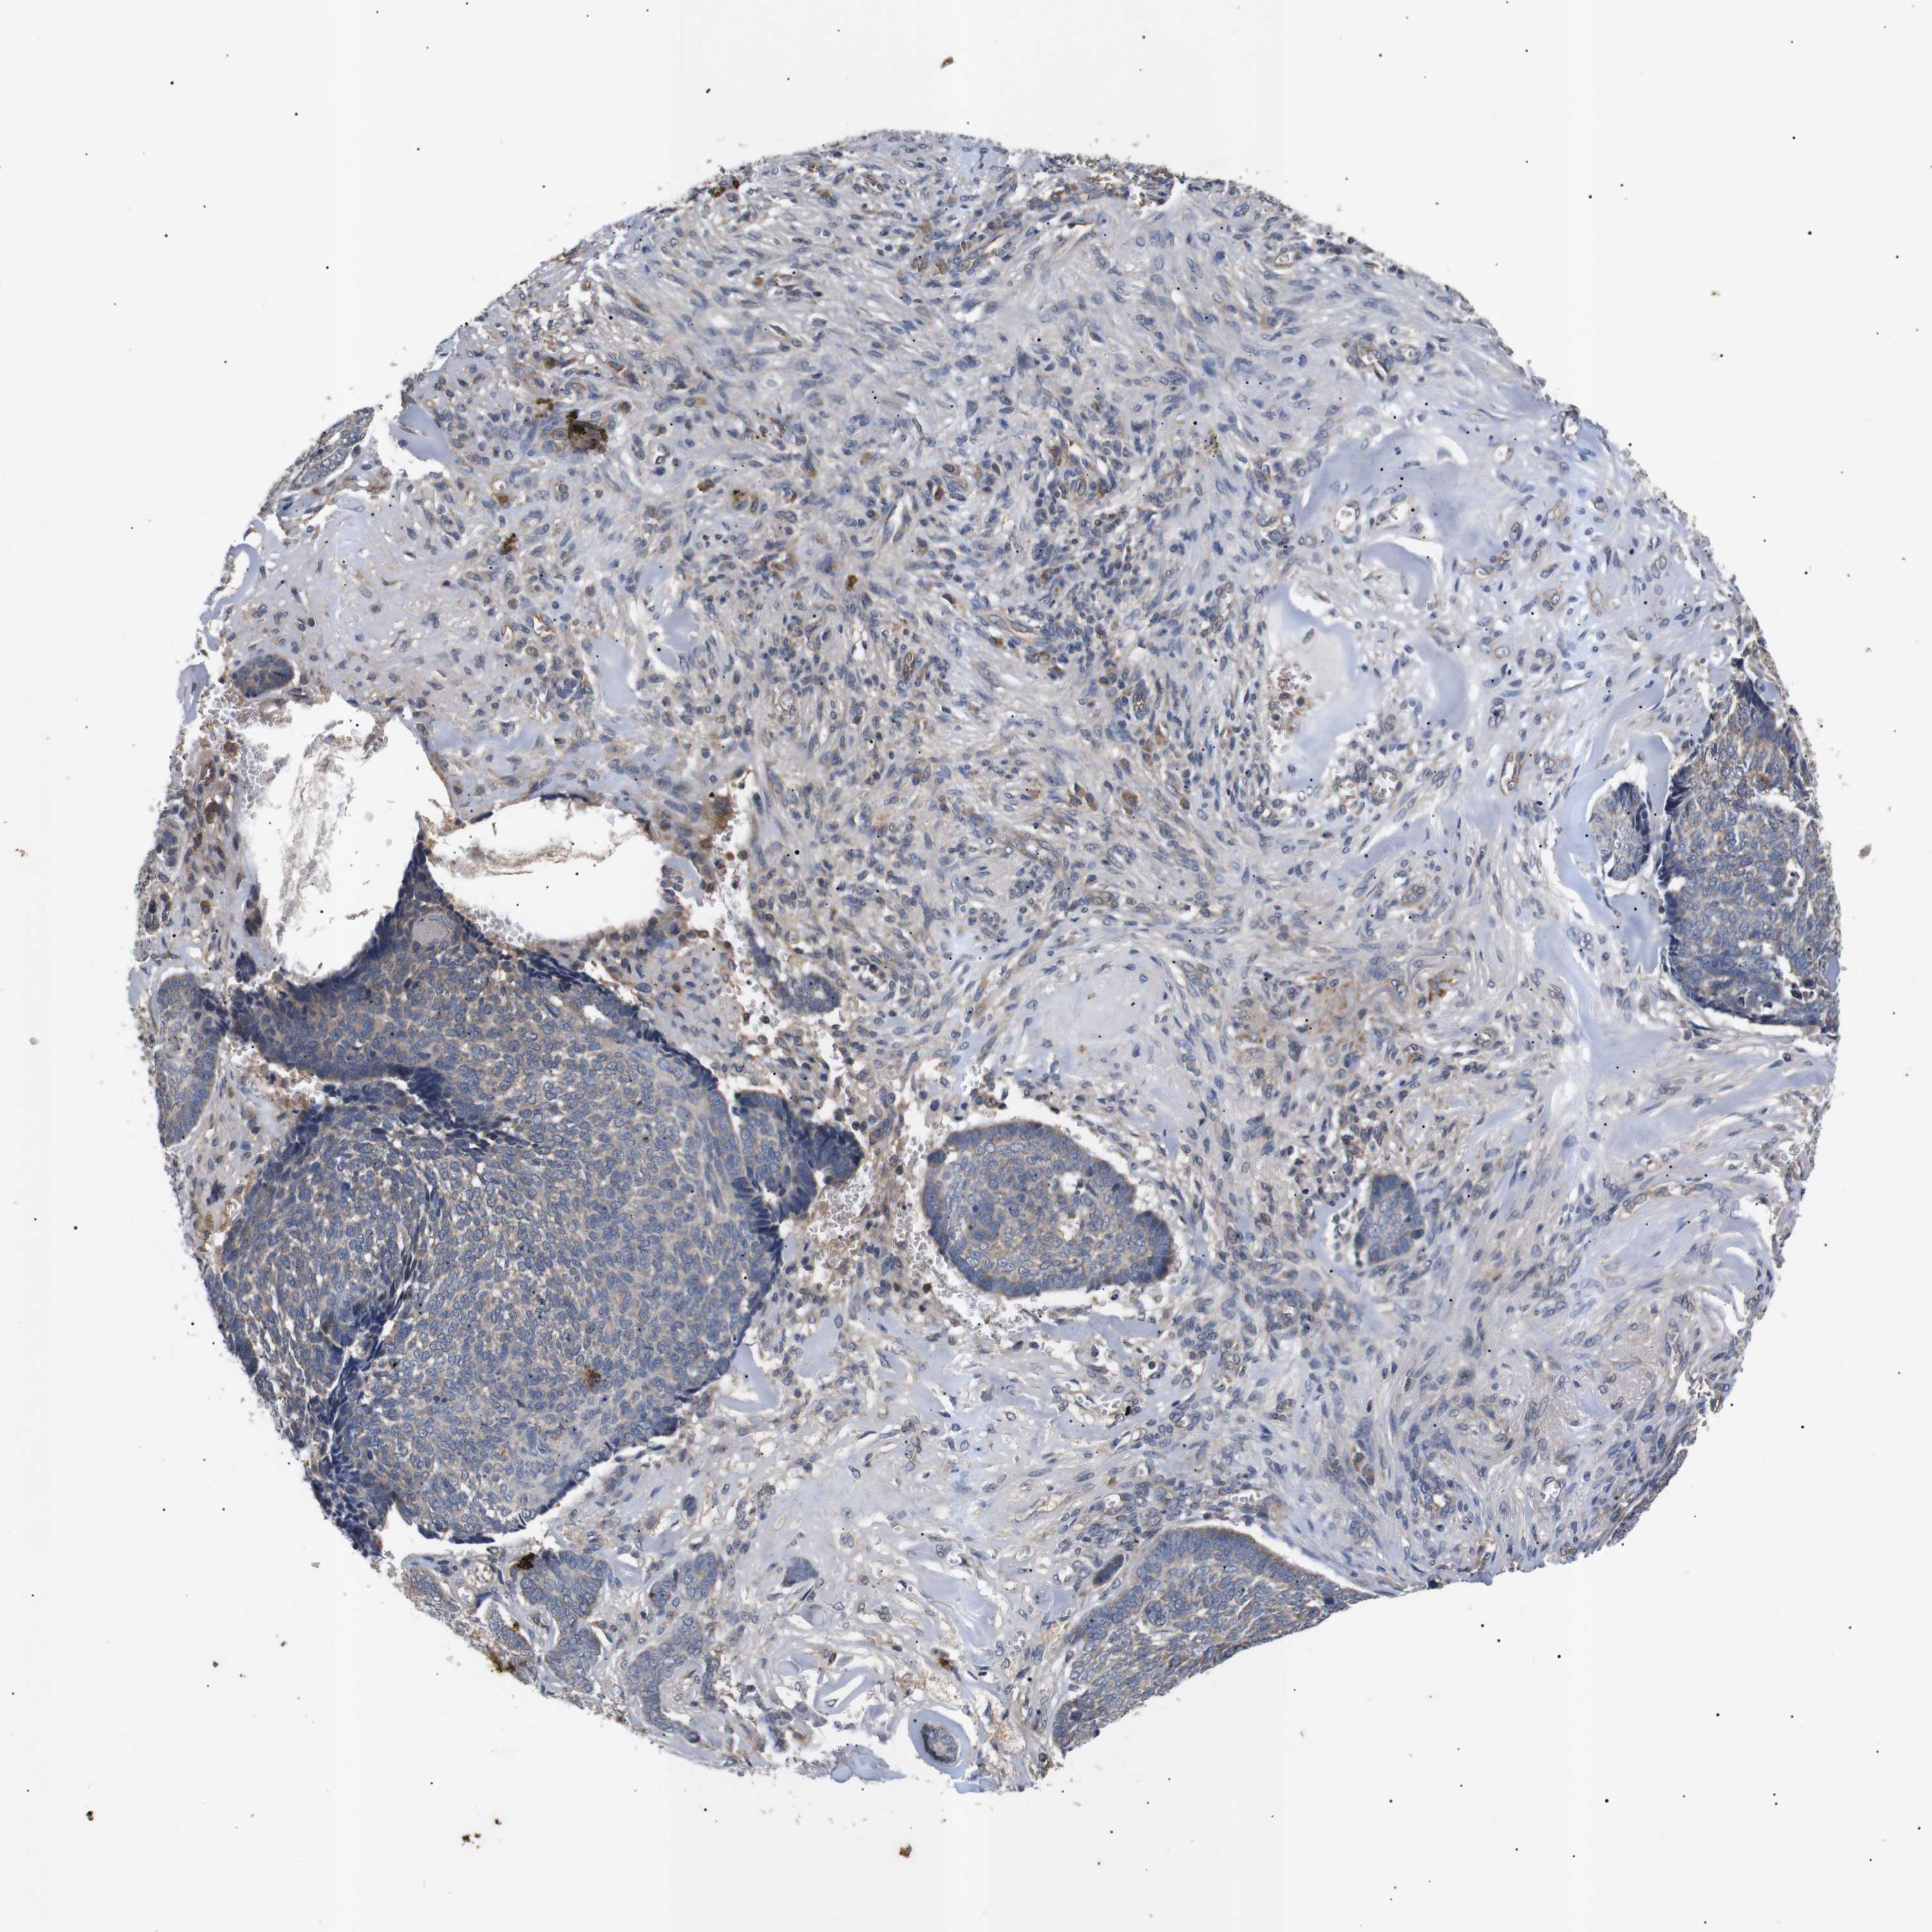

SKIN CANCER - Protein expressioni

A mouse-over function shows sample information and annotation data. Click on an image to view it in a full screen mode. Samples can be filtered based on level of antibody staining by selecting one or several of the following categories: high, medium, low and not detected. The assay and annotation is described here.

Each image is clickable and will lead to virtual microscopy that enables deeper exploration of all samples and also displays staining intensity scores, fraction scores and subcellular localization as well as patient and tissue information for each sample.

Antibody CAB010302

High

Medium

Strong

Moderate

>75%

75%-25%

Location

Cytoplasmic/membranous

Squamous cell carcinoma, NOS

Squamous cell carcinoma, metastatic, NOS